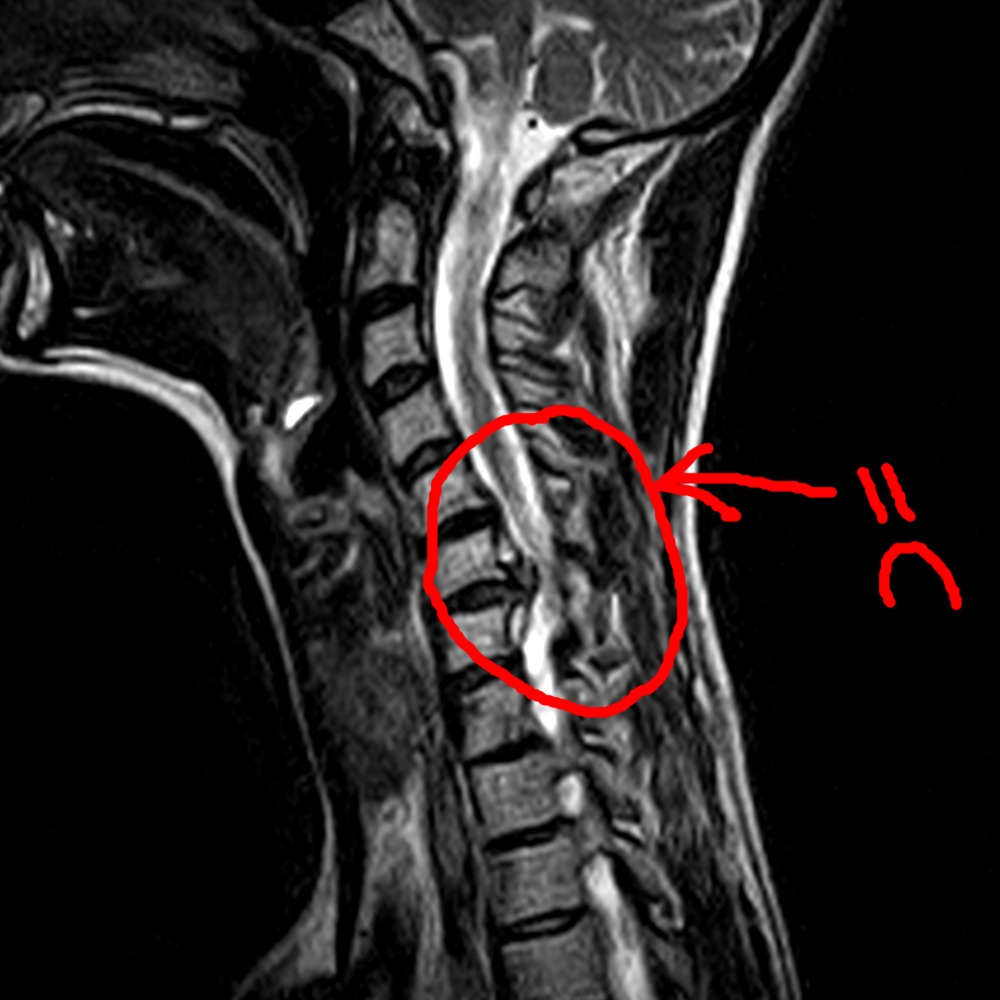

Cervical myelopathy – MRI – Radiology at St. Vincent’s University Hospital

Sagittal T1-weighted MRI of his cervical spine. | Download Scientific …

Mri Of Cervical Spinal Canal Stenosis Stock Photo – Download Image Now …

Preoperative MRI showing moderate spinal stenosis at the L3/4 level (a …